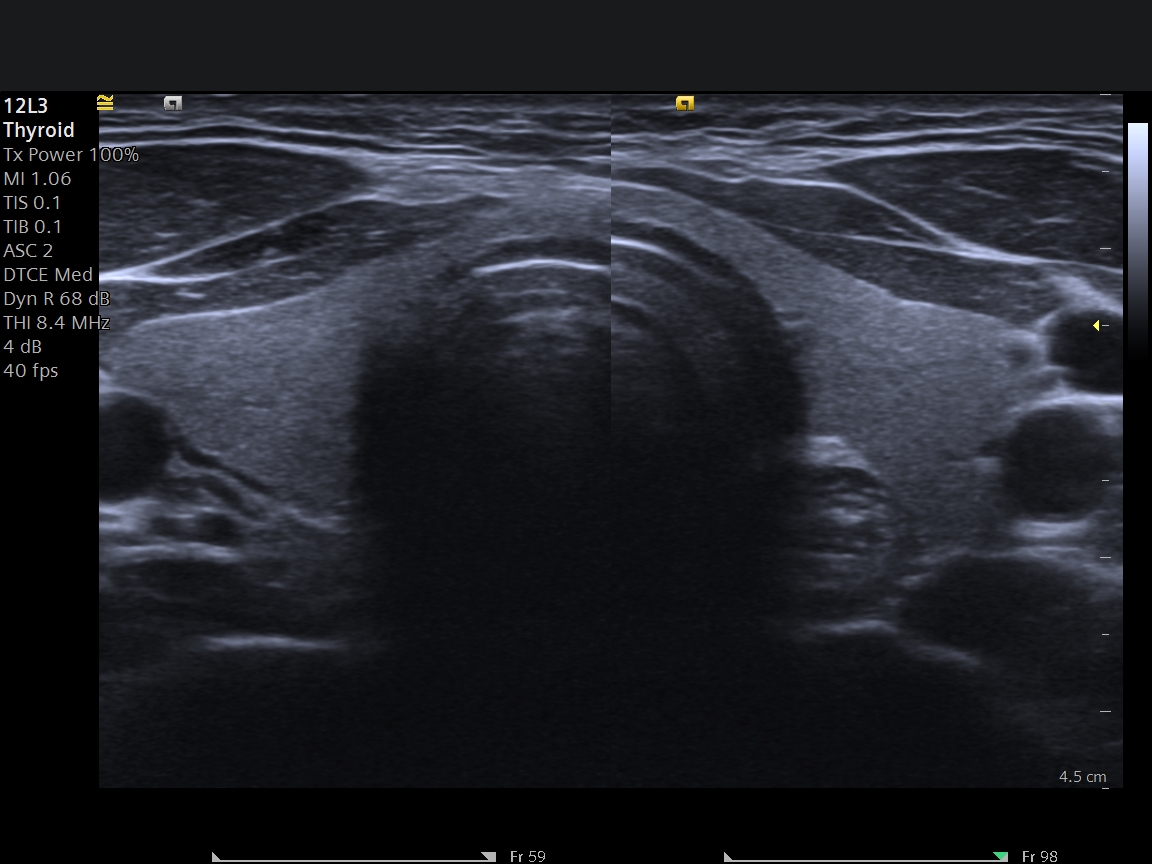

USG Eşliğinde Tiroid Biyopsisi Nedir?

Tiroid nodülü, toplumda oldukça sık görülen bir durumdur. Özellikle kadınlarda ve 40 yaş sonrası bireylerde tiroid bezinde nodül saptanma oranı artar. Mersin'de tiroid nodülü nedeniyle başvuran hastaların en sık sorduğu soru ise şudur: "Bu nodül tehlikeli mi?"